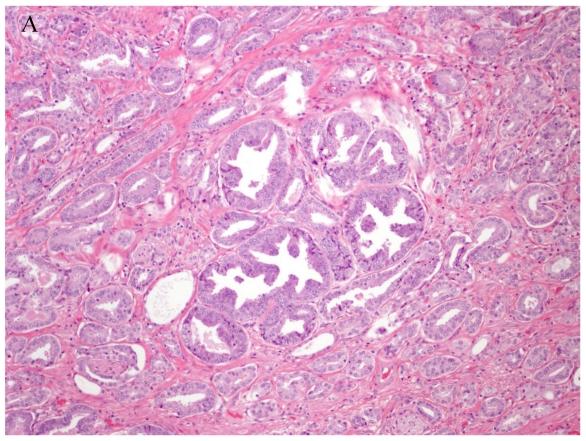

人类癌症分类:一种整合形态学、癌症干细胞、蛋白质组学和基因组学的系统生物学模型。

Human cancer classification: a systems biology- based model integrating morphology, cancer stem cells, proteomics, and genomics.

Human cancer classification is currently based on the idea of cell of origin, light and electron microscopic attributes of the cancer. What is not yet integrated into cancer classification are the functional attributes of these cancer cells. Recent innovative techniques in biology have provided a wealth of information on the genomic, transcriptomic and proteomic changes in cancer cells. The emergence of the concept of cancer stem cells needs to be included in a classification model to capture the known attributes of cancer stem cells and their potential contribution to treatment response, and metastases. The integrated model of cancer classification presented here incorporates all morphology, cancer stem cell contributions, genetic, and functional attributes of cancer. Integrated cancer classification models could eliminate the unclassifiable cancers as used in current classifications. Future cancer treatment may be advanced by using an integrated model of cancer classification.

目前,人类癌症的分类基于细胞起源、癌症的光镜和电镜特征的概念。尚未纳入癌症分类的是这些癌细胞的功能特征。生物学的最新创新技术为癌细胞的基因组、转录组和蛋白质组变化提供了丰富的信息。癌症干细胞概念的出现需要纳入分类模型,以捕获已知的癌症干细胞属性及其对治疗反应和转移的潜在贡献。这里提出的癌症综合分类模型纳入了所有形态学、癌症干细胞贡献、遗传和癌症功能属性。综合癌症分类模型可以消除当前分类中使用的不可分类癌症。使用癌症分类的综合模型可能会推进未来的癌症治疗。